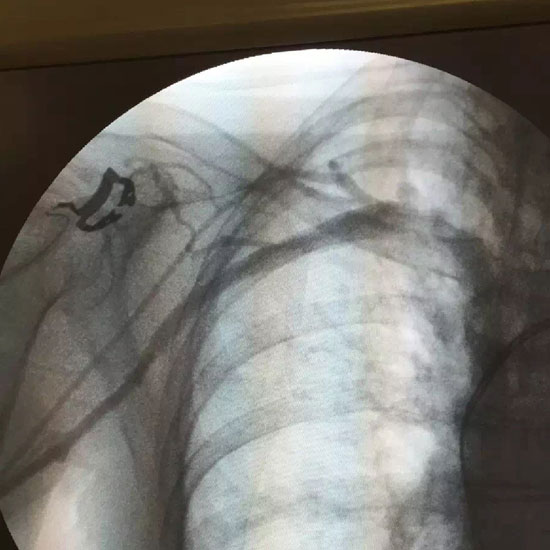

医疗影像

医疗影像。

刘秀实供图